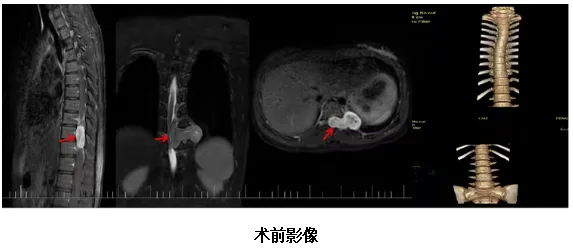

胸椎增强+MRA示胸10-11椎体左旁髓外硬脑膜下占位,神经鞘瘤可能性大。